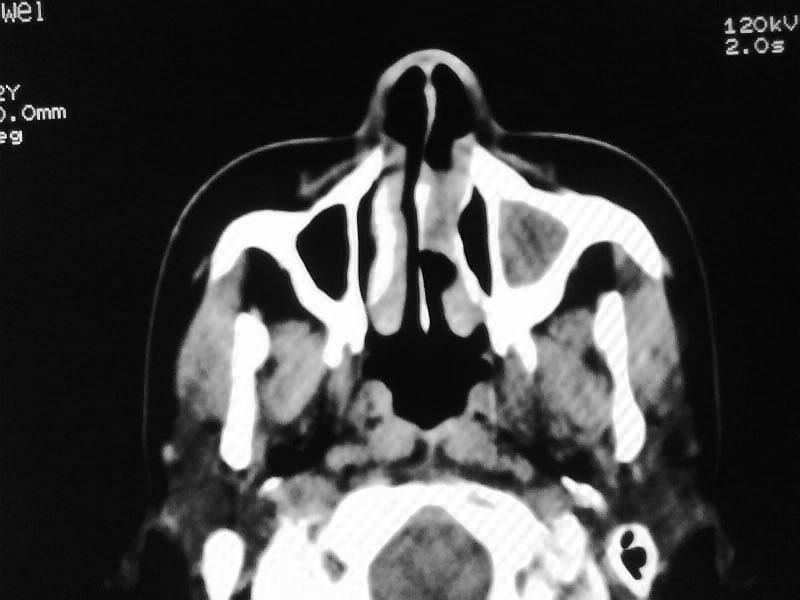

以下是引用zjzjr在2009-5-3 9:59:00的发言:[br]左侧鼻腔息肉、左侧筛窦、上颌窦炎症。双侧下鼻甲粘膜肥厚。

以下是引用随光逐影在2009-5-3 13:02:00的发言:[br]1)左侧鼻腔新生物(息肉可能)。2)左侧上颌窦及左侧筛窦炎症。3)双侧下鼻甲黏膜肥厚。